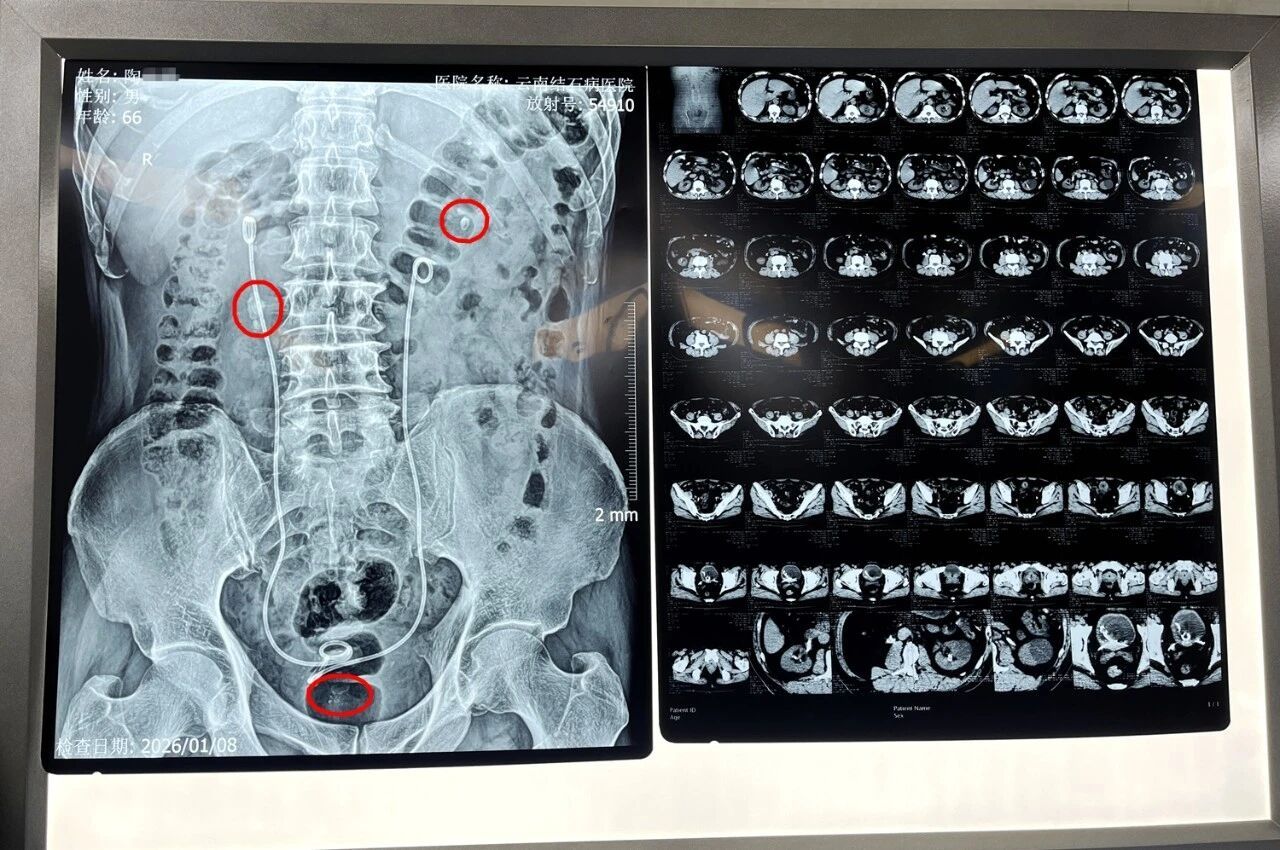

经初步对症处理缓解症状后,为寻求进一步治疗,陶先生慕名来到云南结石病医院。经系统检查,他被确诊为:前列腺增生、右输尿管多发结石伴右肾积水、双肾多发结石、膀胱多发结石,并伴有严重尿潴留。医院首席专家王力教授指出,其前列腺中叶突入膀胱近2厘米,是导致尿潴留的关键原因。

术中,王力教授与黄鸿宾主任先通过瑞梦手术,精准消融患者前列腺左右两叶的增生组织;继而采用双极等离子电切术,将前列腺中叶突入膀胱部分进行精细切除;随后再通过输尿管镜与纤维输尿管镜,将右侧输尿管上段结石、右肾结石及膀胱内结石击碎取出。整台手术历时两个多小时,顺利完成。